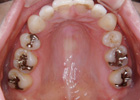

歯を抜いて治療した例 その2

治療前

治療後